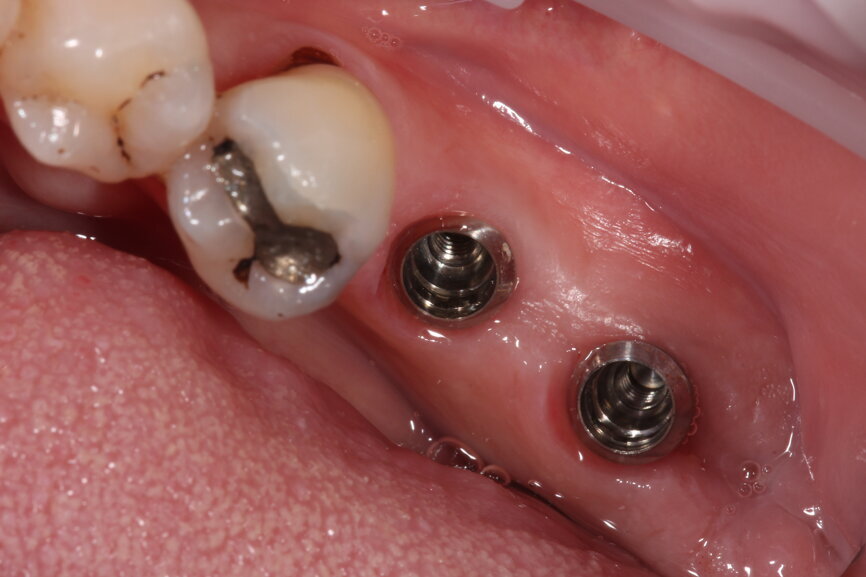

Fig. 9: Surgical placement of LL67 implants.

Fig. 11: Tissue level implants.

Once the implants are placed in situ and fully integrated, we then have a choice of conventional wet impression techniques versus digital intra-oral scanning. For the majority of cases, intra-oral scanning is extremely predictable and reliable—more so than conventional techniques—with milled (and lately printed) models having excellent properties and less accumulation of processing errors. However, deeply placed implants relative to adjacent teeth with deep contact points are very difficult to scan and pick up. Straumann tissue level implants offer a very straightforward restorative platform to scan from.